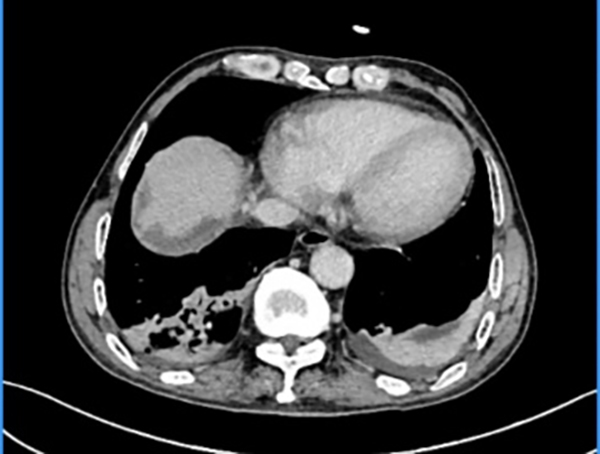

术后复查影像显示

下腔静脉血流通畅、充盈良好

在多学科团队的紧密协作下,手术最终取得圆满成功。患者术后转入重症医学科接受精心监护,生命体征平稳,顺利渡过了手术危险期。术后第4天,增强CT检查显示患者下腔静脉管腔通畅、血流充盈良好,无狭窄及血栓形成。最终的病理学检查报告证实:肿瘤及癌栓均被完整切除,手术切缘阴性(R0切除),达到了根治性效果。患者术后恢复顺利,术后第9天出院。